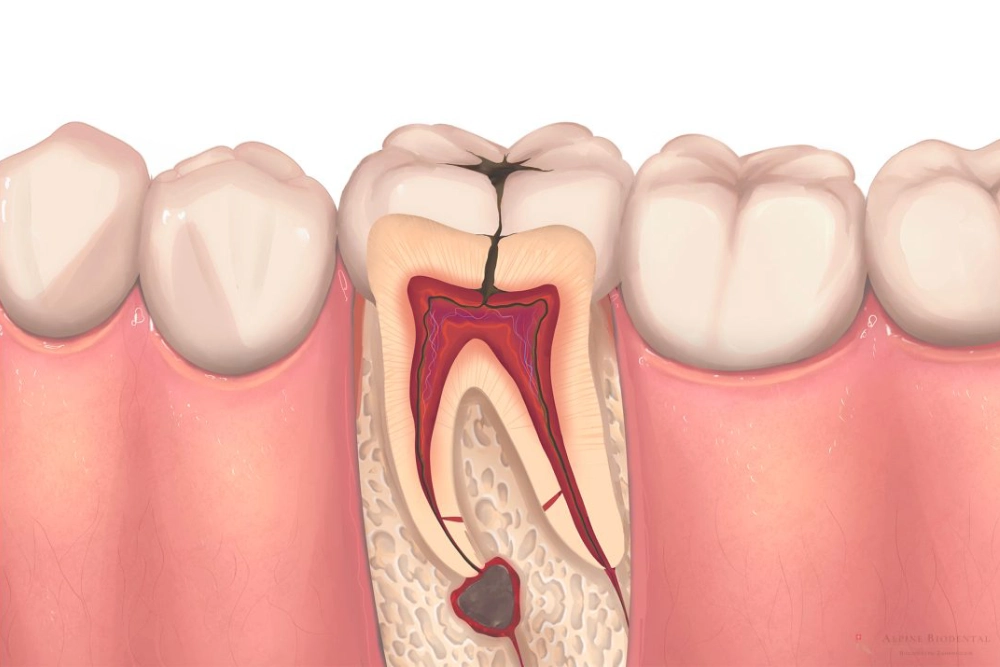

A root canal can save a badly infected tooth by removing the infection and stopping the pain at its source. This treatment is often the quickest way to relieve severe toothaches.